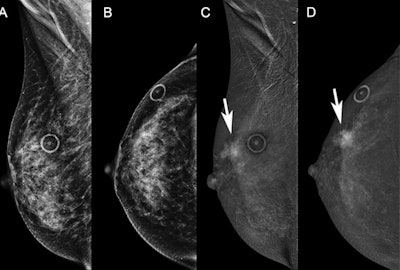

Diagnostic contrast-enhanced mammograms (CEM) were performed on a 58-year-old woman recalled from screening for possible right breast distortion. Low-energy images on (A) mediolateral oblique and (B) craniocaudal views are unremarkable and the distortion did not persist. Recombined images show incidental mass enhancement (arrow) in the upper outer right breast on (C) mediolateral oblique and (D) craniocaudal views. These are examples of two-view recombined-only findings. Images courtesy of RSNA.The study authors also wrote that using BI-RADS MRI lexicon to describe CEM recombined imaging findings showed "remarkably high" interobserver agreement (0.84) and can be used as a foundation for CEM BI-RADS. The team also reported that background parenchymal enhancement (p = 0.19) and breast density (p = 0.28) were not associated with enhancement type.

Out of these, 190 CEM studies showed enhancement findings. The researchers found that enhancing lesions were more likely to be malignant when associated with low-energy findings (26% vs. 59%) (p = 0.001).

The team also found that among enhancement types, mass enhancement composed 71% (99 of 140) of all malignancies with a PPV of 63% when linked to low-energy findings. Foci, non-mass enhancement, and mass enhancement without low-energy findings had PPVs of 6%, 24%, and 38%, respectively. Non-mass enhancement was also more likely to be benign overall (PPV, 43%), but the likelihood of malignancy was higher (PPV = 82%) when linked to calcifications.